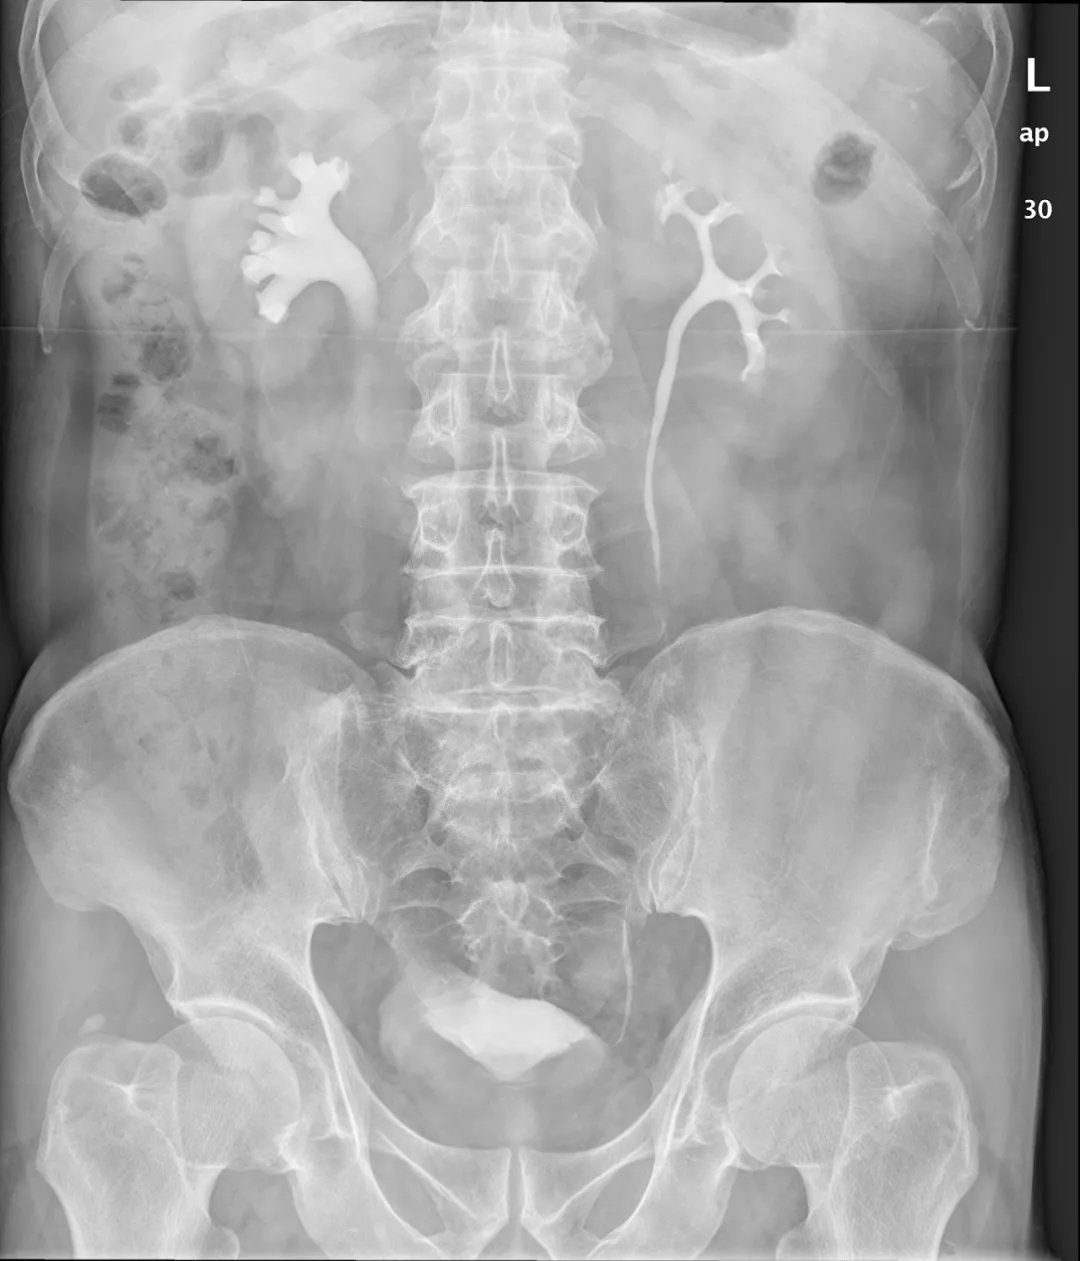

湖北男子双侧输尿管结石梗阻致双肾积水,专家:恐危及肾功能